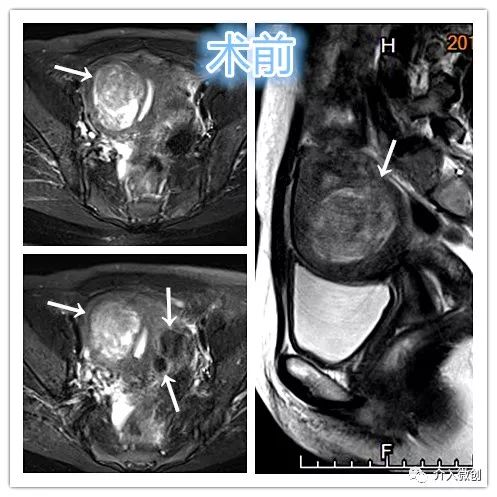

中年妇女,因子宫肌瘤导致长期的月经量明显增多、经期延长,最终导致严重贫血。

- MRI检查显示子宫多发肌瘤。

MRI检查示肌壁间型子宫肌瘤

- DSA下行双侧子宫动脉栓塞治疗。

左侧子宫动脉造影

右侧子宫动脉造影

- 术后患者月经量过多明显缓解,贫血症状逐步自行改善。